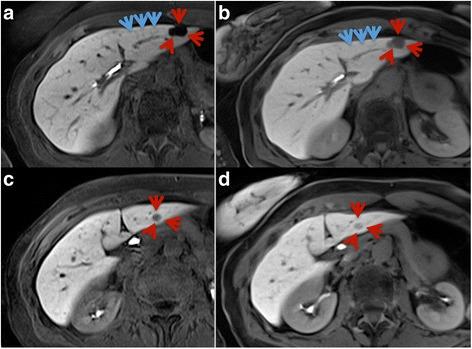

Twenty minutes after administration of a HSCA (gadoxetic acid), a T1-weighted VIBE sequence with radial k-space sampling (radialVIBE, 180 s acquisition time in free breathing) and a highly accelerated Cartesian VIBE with Dixon fat separation (CD-VIBE, CAIPIRINHA acceleration with r = 2 × 2, breath-hold 8-10 s) were acquired in 35 patients (12 female, 57 ± 13 years), who showed breath-holding difficulties in early phases of the examinations. Image quality (image sharpness, noise, artifacts, homogeneity of fat saturation, bile duct delineation and overall image quality) as well as conspicuity and liver-to-lesion signal intensity (SI) ratios of focal liver lesions were assessed for both radial- and CD-VIBE.

在给予HSCA(钆塞酸)20分钟后,对35例患者(12例女性,年龄57±13岁)进行了具有径向k空间采样的T1加权VIBE序列(radialVIBE,自由呼吸下采集时间为180秒)和具有狄克逊脂肪分离的高度加速笛卡尔VIBE序列(CD-VIBE,CAIPIRINHA加速,r = 2×2,屏气8 - 10秒),这些患者在检查早期存在屏气困难。对radialVIBE和CD-VIBE序列的图像质量(图像清晰度、噪声、伪影、脂肪抑制均匀性、胆管轮廓和整体图像质量)以及局灶性肝病变的显眼程度和肝脏与病变的信号强度(SI)比值进行了评估。

结果

两个序列的整体图像质量均被评为良好至优秀,而在大多数情况下更倾向于CD-VIBE。虽然radialVIBE在图像噪声和伪影方面获得了更好的结果,但在胆管轮廓和清晰度方面两个序列的评分相同。CD-VIBE上局灶性肝病变(n = 42)的显眼程度评分明显更高,SI比值也明显更高(radialVIBE中为1.61±0.70,CD-VIBE中为2.45±1.44,p = 0.0001)。在三名患者中,CD-VIBE由于严重的呼吸伪影被评为无法诊断,而radialVIBE在这些患者中具有诊断价值。